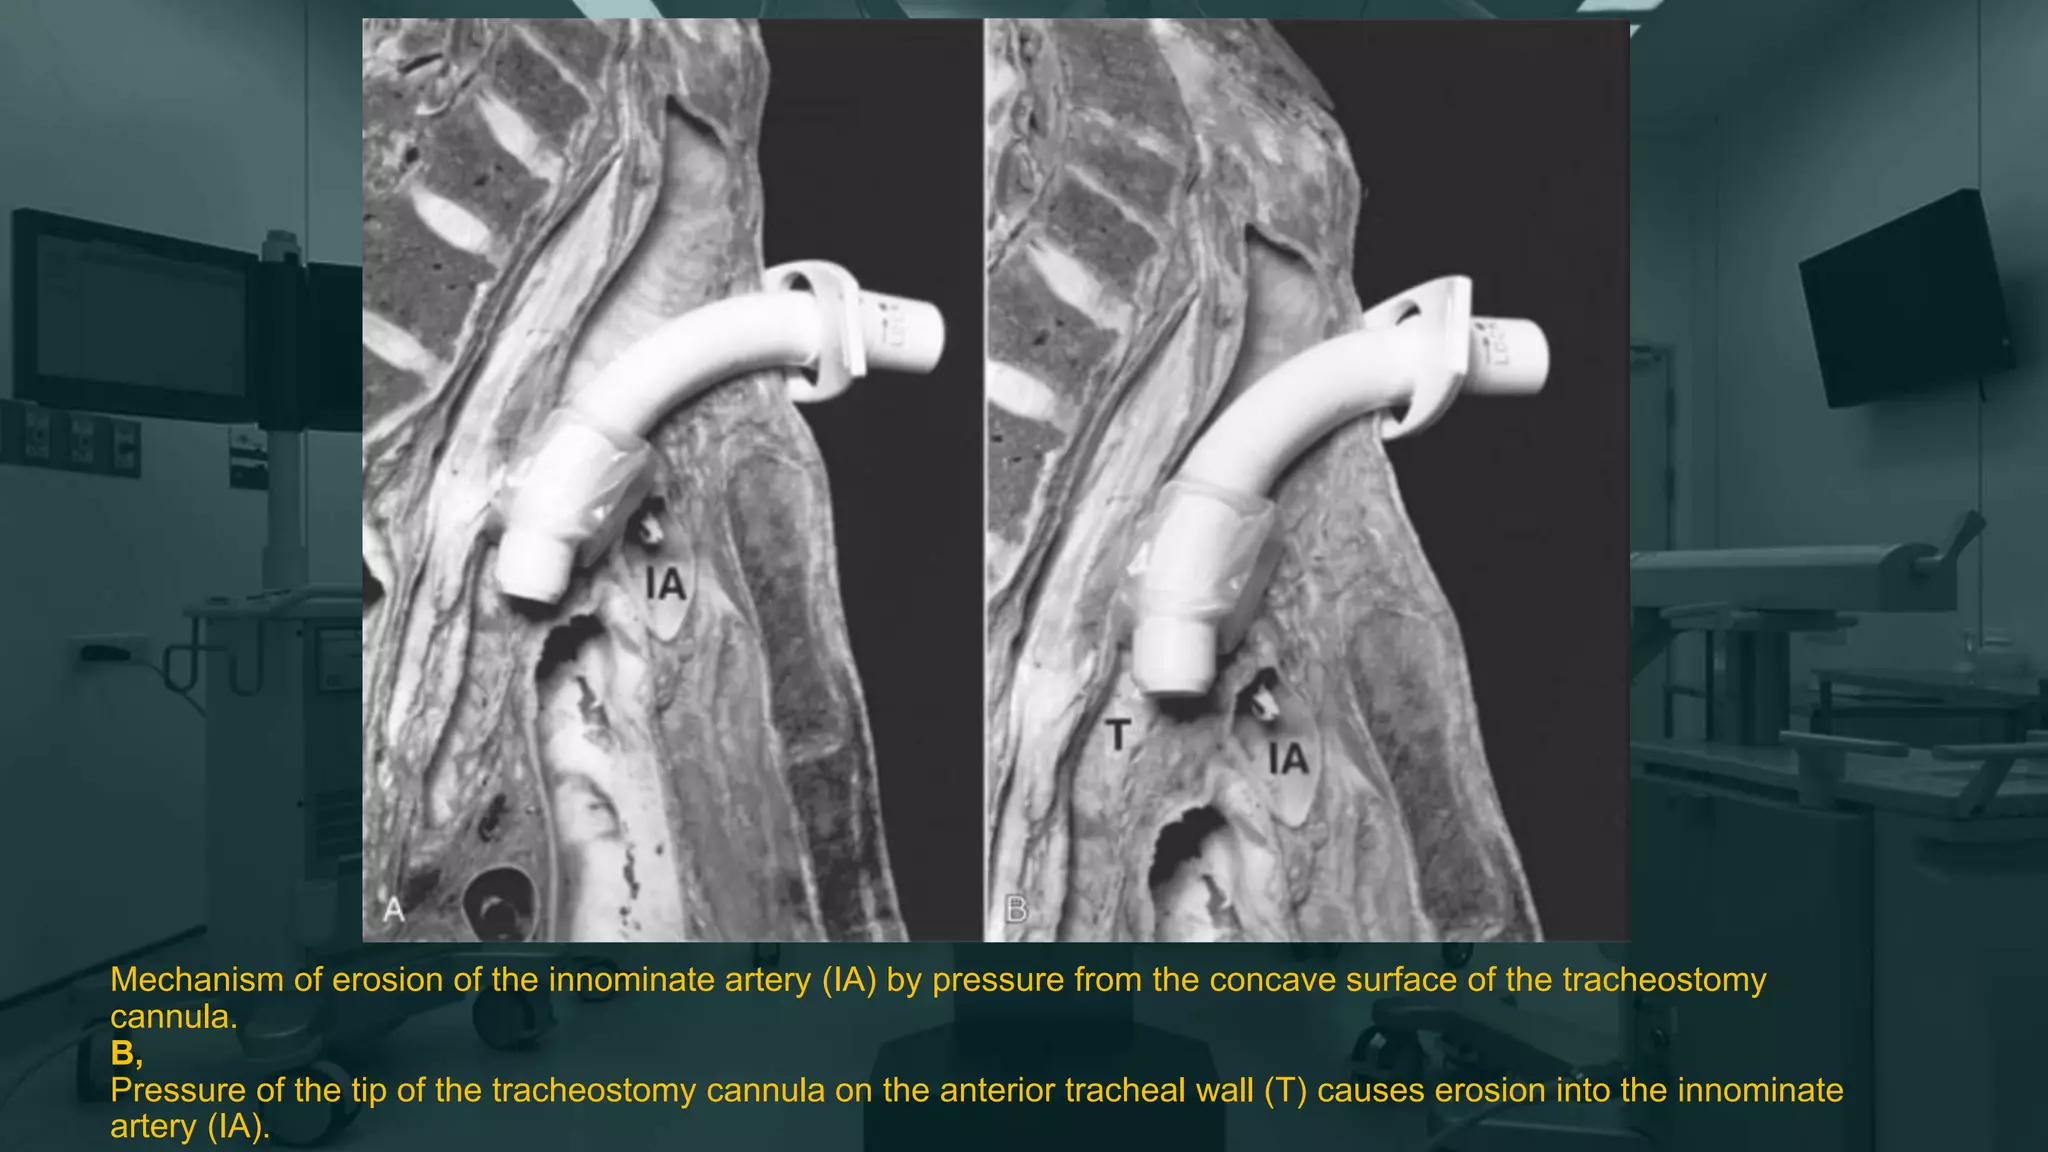

Mechanism of erosion of the innominate artery (IA) by pressure from the concave surface of the tracheostomy

cannula.

B,

Pressure of the tip of the tracheostomy cannula on the anterior tracheal wall (T) causes erosion into the innominate

artery (IA).